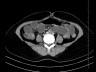

Case of the Week 25 2016 *39-year-old female with abdominal pain and vomiting. What is the most likely diagnosis? Answer Answer: Small bowel obstruction caused by intussusception produced by an ileal lipoma. Kategori:Cases Önceki yazı Case of the Week 21 2016 Sonraki yazı Case of the Week 26 2016